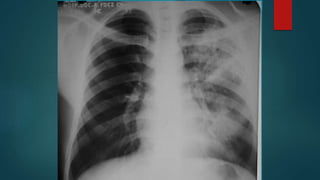

Radiografía

de Tórax

Patrón Alveolar

Patrón Bronconeumónico

Patrón Intersticial